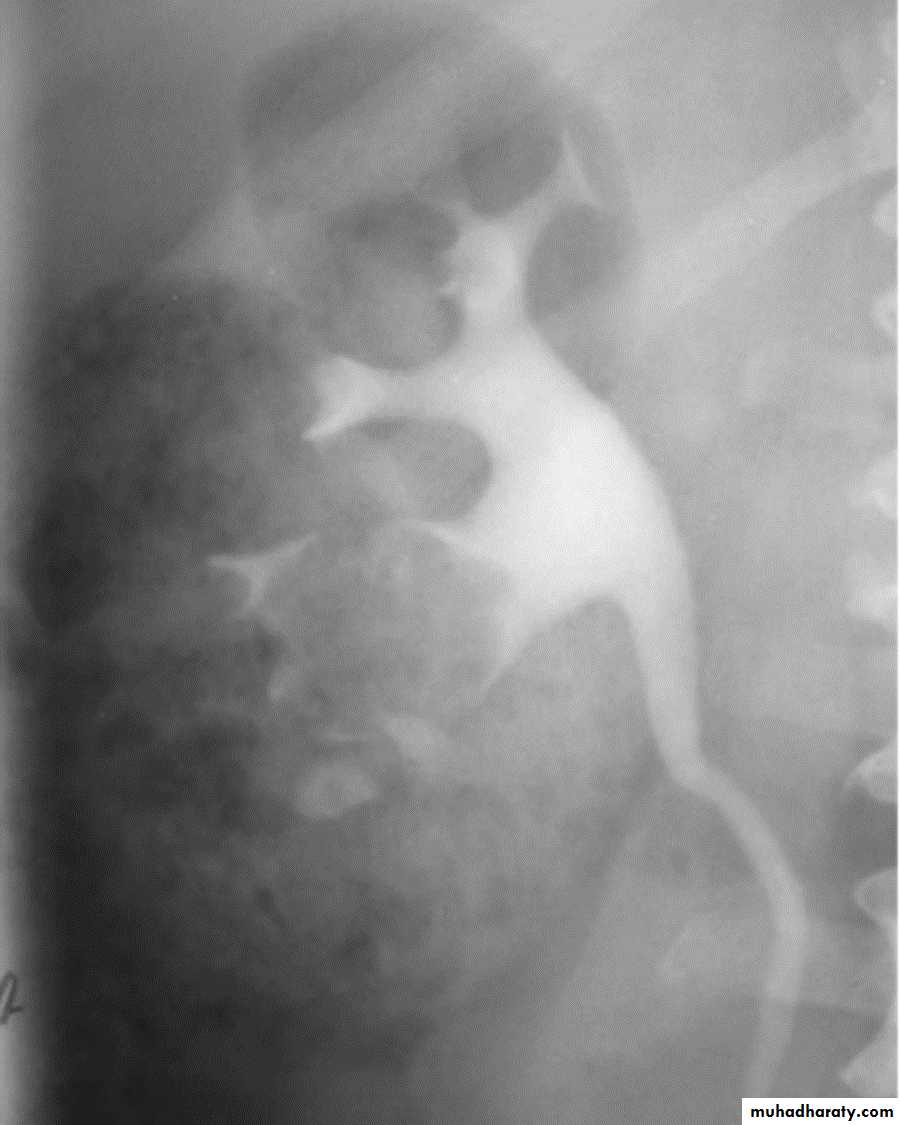

IVU excretory phase showing marked dilated PCS , but normal ureter …

DX congenital PUJ obstruction.Renal masses